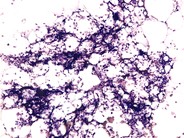

A 73-year-old man without prior personal or family history of anemia developed a chronic hemolytic anemia characterized by an absolute reticulocyte count of 347 000/mm 3 (13%) and spherocytic red-cell morphology (see panel A). Antiglobulin testing was negative but osmotic fragility testing was positive. Bone marrow biopsy was hypercellular with a decreased M:E ratio and dysplastic erythroid precursors. Standard cytogenetics reported an interstitial deletion of 5q13-33 and a gain of material on 14q22. High-density single-nucleotide polymorphism array–based karyotyping revealed 6 deletion regions on chromosome 5 and 3 deletion regions on chromosome 14, including loss of 14q23.1-24.2. Taken together with the cytogenetic studies, a complex rearrangement of chromosomes 5 and 14 resulted in the net losses. One of the 14q-deletion regions contains SPTB, rendering this patient haploinsufficient for the gene encoding the β-spectrin protein. Thus, this patient’s complex rearrangement resulted in a phenocopy of hereditary spherocytosis type 2 (OMIM ) (see panel B). This patient’s case demonstrates the clinical utility of high-density array karyotyping to define atypical clinical presentations and highlights the variable natural history of myelodysplastic syndromes.(Panel A) Blood smear from a 73-year-old man with a myelodysplastic syndrome and acquired spherocytosis. (Panel B) Blood smear from a 65-year-old man with autosomal-dominant hereditary spherocytosis. Red arrows indicate microspherocytes and blue arrows indicate polychromatophilic cells (reticulocytes).